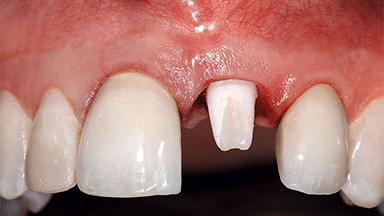

A healthy 37-year-old female patient was referred for a consultation on the replacement of missing tooth 21 with an implant-supported restoration. She stated that several years previously the tooth had been traumatically avulsed following a motor vehicle accident. The tooth was replaced with a three-unit fixed partial denture (FPD) immediately afterwards. Over time, she became disillusioned with the FPD and looked for a different option, including orthodontic therapy. She presented still in her orthodontic appliances, with the pontic sectioned free from the FPD but attached to the archwire. Her orthodontist felt that orthodontic treatment had been successfully completed, but nevertheless referred her before removing the appliances in case adjustments were necessary.

Defining Characteristics One missing tooth to be replaced by an implant-borne prosthesis

Defining Characteristics One missing tooth to be replaced by an implant-borne crown